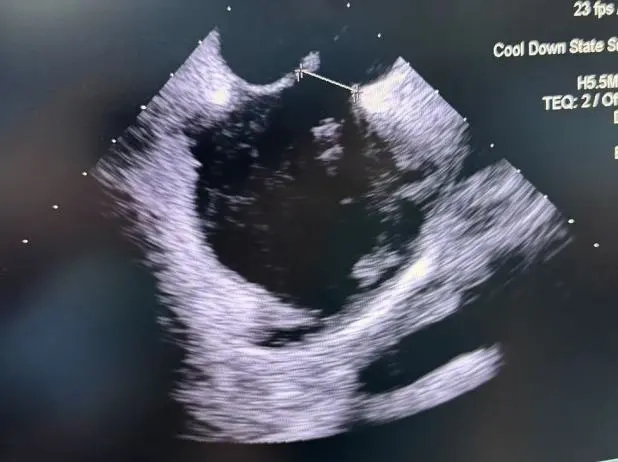

展开左盘面

推出左盘3个Mark及腰部Mark,牵拉成型线使左盘面成型

后撤钢缆和鞘管,使左盘面贴靠房间隔

超声下,封堵器左右盘面贴合房间隔两侧